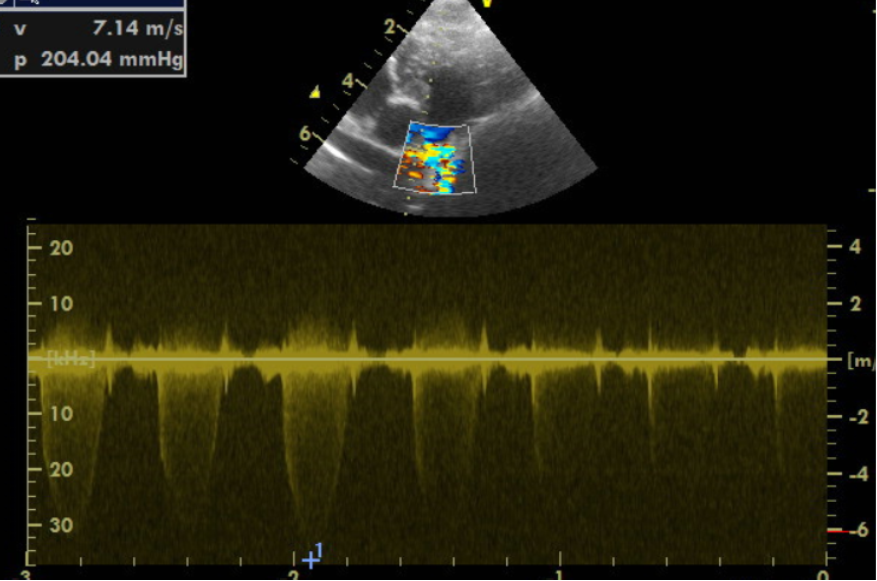

Im Herzultraschall zeigte sich eine hochgradig verdickte Muskulatur der Kammerwände der rechten Hauptkammer aufgrund einer hochgradigen Druckerhöhung. Es offenbarten sich außerdem angeborene Veränderungen der Mitralklappen und der Trikuspidalklappen. Bei der Darstellung der Pulmonalarterie zeigte sich eine missgebildete Pulmonalklappe, die wenig beweglich war. Zudem schloss und öffnete sie sich nicht vollständig. Die hochgradige Verwachsung der Pulmonalklappenöffnung führte zu einem sehr starken Anstieg des Blutdrucks von normalerweise 20 mmHg (Millimeter Quecksilbersäule) auf über 200 in der rechten Hauptkammer. Außerdem war der Klappenring der Pulmonalarterie sehr eng angelegt, wodurch der Schweregrad zusätzlich negativ beeinflusst wurde.

Bei Gonzo konnte der hochgradige Druckgradient von initial über 200 mmHg um mehr als 50 % auf 75 mmHg gesenkt werden. Dies stellt einen überaus erfolgreichen Verlauf des Eingriffes dar. Gonzos Druckgradient in der rechten Hauptkammer konnte vom hochgradigen Bereich erfolgreich auf einen mittelgradig erhöhten Druckgradienten gesenkt werden! Dies bedeutet für Gonzo, dass durch den Eingriff, der minimalinvasiv und ohne Eröffnung des Brustkorbs erfolgte, eine normale Lebenserwartung mit normaler Lebensqualität erzielt werden konnte. Der interventionelle Eingriff hat sich für Gonzo und seine Besitzer gelohnt! Fünf Jahre später geht es Gonzo nach wie vor sehr gut.

Je höher der Druck in der rechten Kammer ist, desto hochgradiger wird die Verdickung der Muskulatur im rechten Herzen. Symptome können Schwäche, Synkopen (Ohnmachtsanfälle) oder ein Rechtsherzversagen sein (wie im Falle von Gonzo, der dadurch eine hochgradige Bauchwassersucht entwickelte). Während leicht bis mittelgradig betroffene Patienten eine normale Lebenserwartung haben, erwartet hochgradige Patienten ohne Eingriff in der Regel ein vorzeitiges Ableben. Dabei zählt bereits ein Druckgradient von 80mmHg als hochgradig. Gonzo hatte anfangs einen Druckgradienten von über 200 mmHg! Eine Absenkung durch den Eingriff auf 75 mmHg spricht für einen absolut erfolgreichen Eingriff.